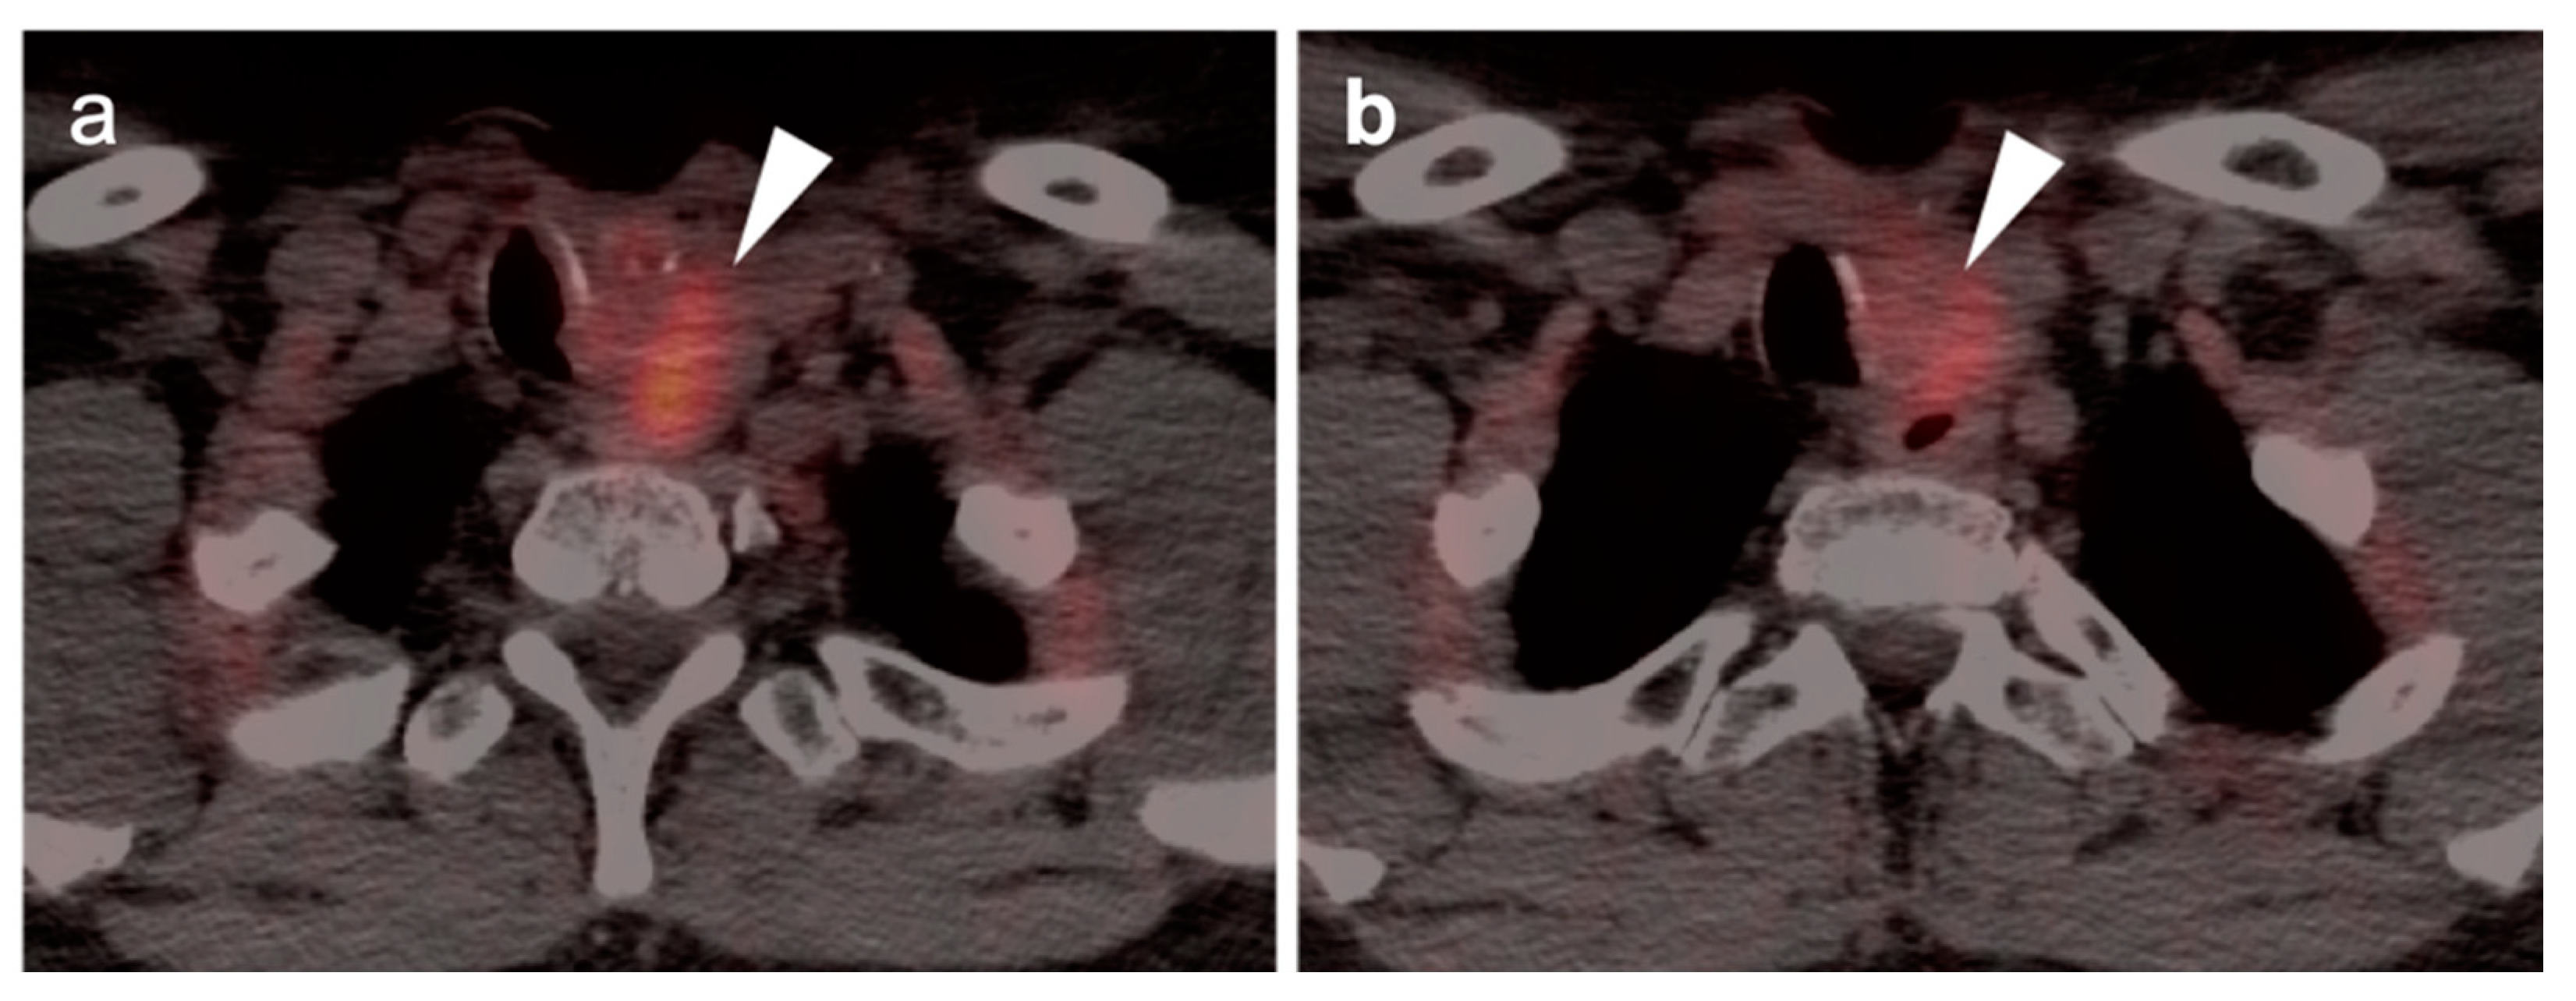

2.6. Thyroid Cancer

- Thyroid Incidentaloma

- 2.

- Differentiated thyroid cancer

- 3.

- Anaplastic thyroid cancer

- 4.

- Medullary thyroid cancer